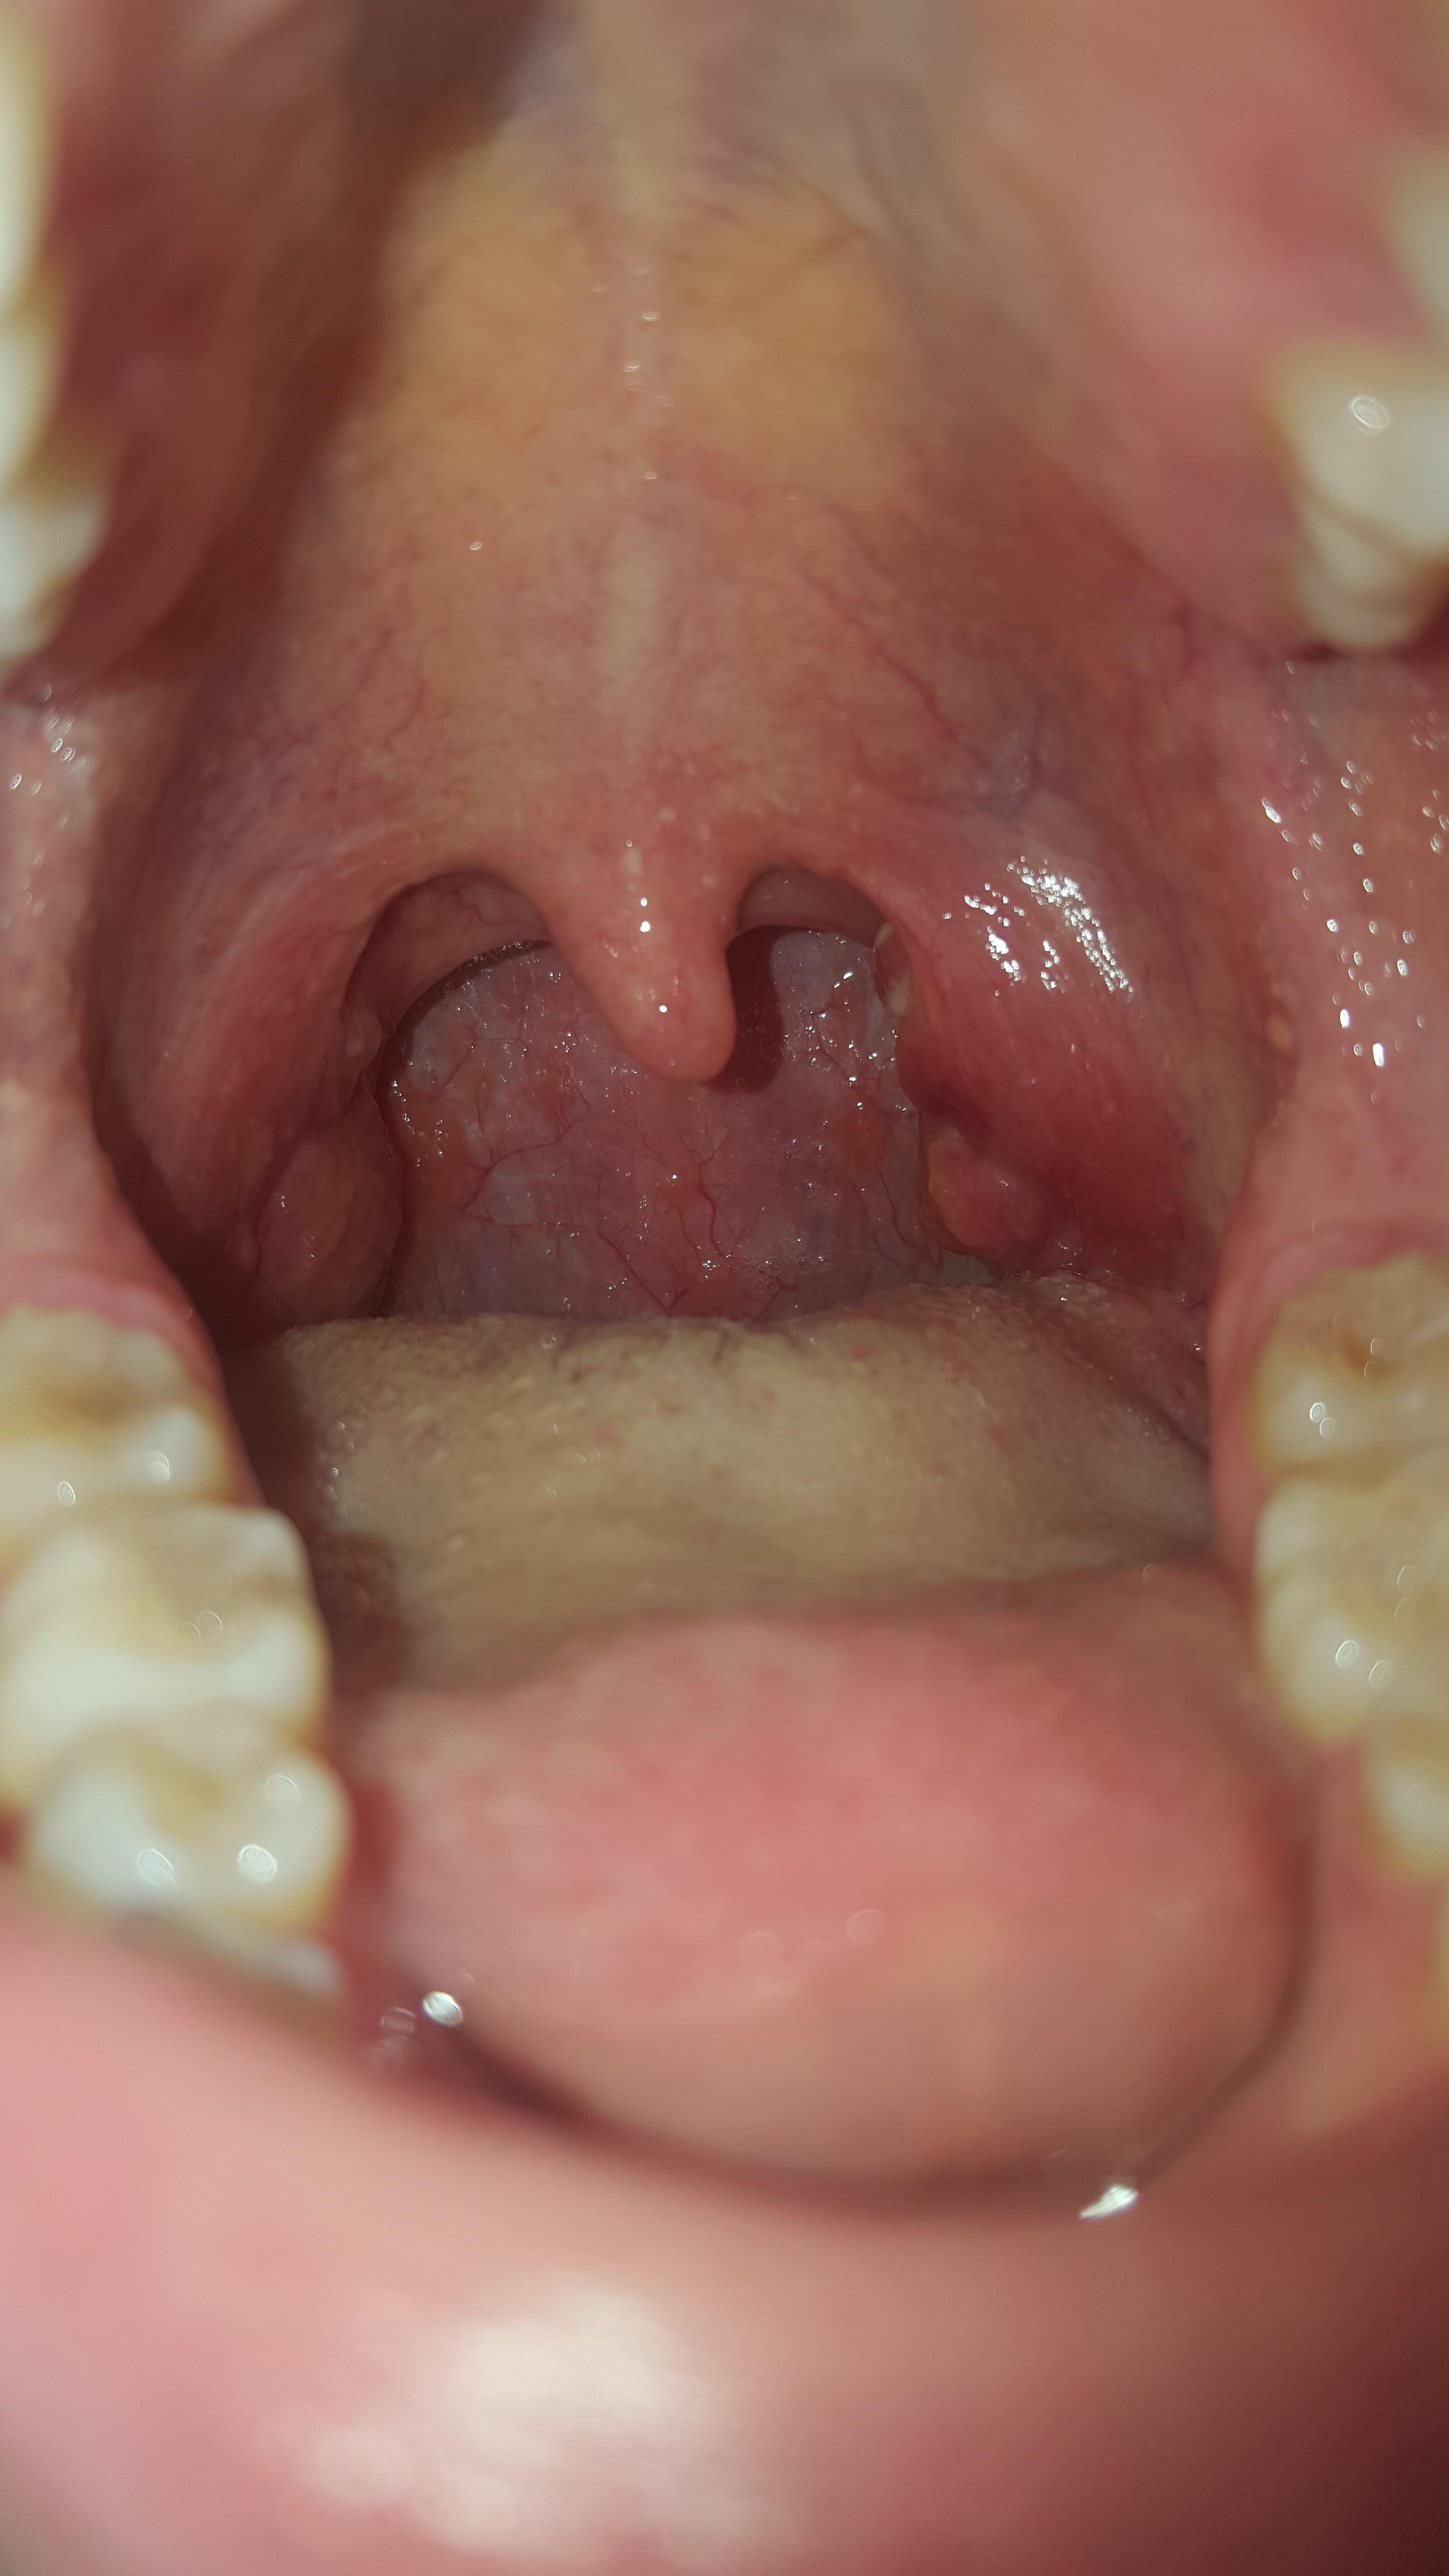

Ja und die Mandel ist auch nicht eitrig oder so, sie ist einfach nur geschwollen und zerklüftet, es sind so komische Rillen drauf Ich hab einen Termin beim HNO in einer Woche Mal sehen, was er zu der Mandel sagt. Wer bei einem fieberhaften Infekt mit dem üblichen Drum & Dran über einen dicken Hals klagt, meint damit meist, dass dieser sich innen geschwollen anfühlt, vielleicht auch wehtut Schuld ist oft eine Mandelentzündung Die Mandeln sind kleine, den Lymphknoten ähnliche Gebilde, die tatsächlich mandelförmig aussehen. Sekret aus Mandel (einseitig), keine Entzündung Liebe Community, ich habe vor Monaten aufgrund eines Fremdkörpergefühls beim Schlucken (rechts) in meinen Hals geschaut und entdeckt, dass meine rechte Mandel größer ist als meine linke.

Der hintere Rachenraum ist gleichmäßig stark gerötet, sowohl die rechte als auch die linke Gaumenmandel ist geschwollen und eventuell vorhandene Eiterauflagerungen finden sich ebenfalls auf beiden Mandeloberflächen Die einseitige Mandelentzündung Die einseitige Mandelentzündung ist nicht so häufig wie die beidseitige. Die entzündeten Mandeln sind hochrot geschwollen und mitunter eitrig, also weiß bis gelblich belegt Auch die Lymphknoten im Kieferwinkel sind oft fühlbar angeschwollen. Seit zwei en habe ich geschwollene Mandeln und Lymphknoten Da mir aber nichts weh tut, will ich deswegen nicht zum Arzt oder ist ein Arztbesuch doch erforderlich, um spätere Komplikationen zu vermeiden?.

Halsschmerzen und geschwollene Mandeln deuten auf eine akute Mandelentzündung (Angina tonsillaris) hin Sanfte Hausmittel können im Anfangsstadium die Beschwerden lindern. Seit etwa 1 1/2 Monaten ist meine rechte Mandel und die rechts liegenden Lymphknoten sind etwas geschwollen (kein Eiter oder so, nur leichte Schwellung und Fremdkörpergefühl beim Scchlucken) und ich fühle mich nicht ganz auf der Höhe. Vergrößerte Mandeln Bei vergrößerten Mandeln handelt es sich um eine vorübergehende oder dauerhafte Schwellung der Gaumenmandeln oder auch der Rachenmandeln Diese kann als Begleitsymptom einer Erkrankung wie beispielsweise eines Infekts auftreten Mit Abklingen dieser schwellen auch die Mandeln wieder ab;.

Termine unter 0306 226 408. Termine unter 0306 226 408. Bei einer Mandelentzündung (Tonsillitis) sind eine oder beide Mandeln gerötet, geschwollen und von einem gelblichweißen Belag überzogen Die Betroffenen klagen über einseitige oder.